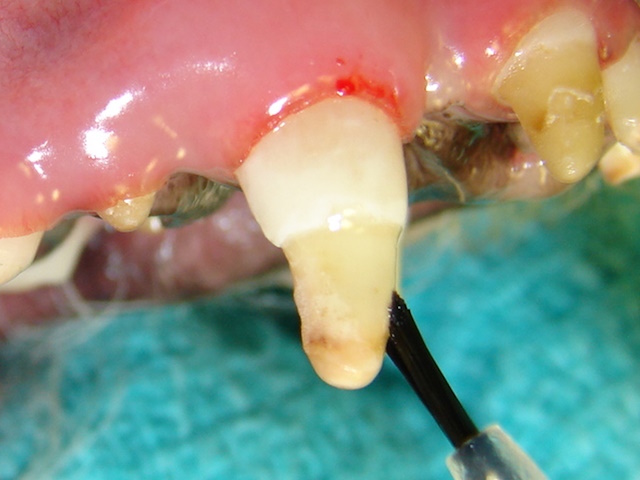

A dentin bonding agent is being applied to the exposed dentin to seal off the dentinal tubules.